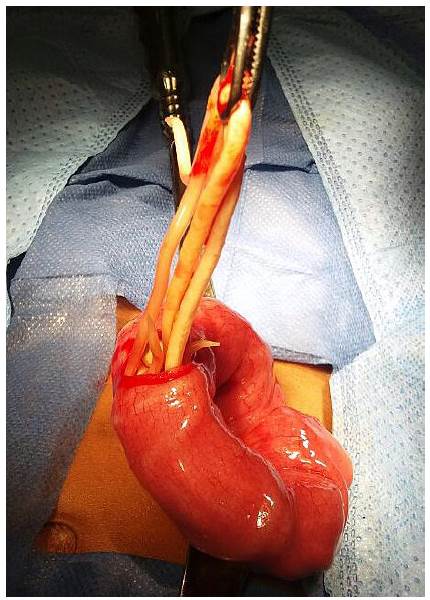

Mediante una sonda nasogástrica (SNG) se eliminó 200 mL de líquido bilioso. Por la sintomatología persistente de OI se decidió una exploración quirúrgica abdominal a través de una incisión transversal infraumbilical derecha. El apéndice tuvo características normales, pero en el íleon, a 20 cm de la válvula ileocecal se encontró un apelotonamiento de AL (foto 2), imposible de movilizar al colon mediante taxis.

Por esta razón se realizó una enterotomía (foto 3) para retirar los parásitos (foto 4).